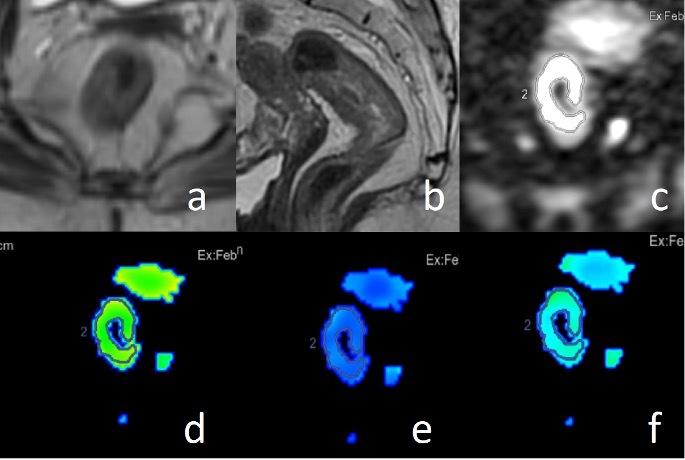

In DWI, three consecutive region of interest (ROI) measurements were performed manually at the widest solid component of the tumor, with exclusion of cystic or necrotic components. The average of these three ROIs was estimated. D, D*, f, and ADC values were calculated from each measurement (Figures 1 and 2).

Figure 1

Axial (A) and sagittal (B) T2-weighted images, diffusion-weighted imaging (DWI) (C), and intravoxel incoherent motion-DWI parameter maps including true diffusion (D), pseudo-diffusion coefficient (E) and perfusion fraction (F) in a patient with rectal cancer